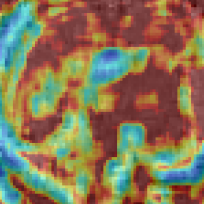

We additionally perform preliminary experiments towards integrating network-based SR components more tightly with an SVR pipeline by investigating the ability of the network to upsample LR voxel intensities that result from an initial volume reconstruction iteration. Successful integration of an iterative (learning-based) SR and volume reconstruction loop will facilitate the well understood mutual benefits of reduced-motion SR input and improved input fidelity for the motion correction task. Qualitative comparison of () LR volume-reconstructed input and resulting upsampled results are found in Fig.3. The benefit of learning the upsampling with modality specific data can be observed to manifest as sharper edge gradients and improved high frequency signal components. The visual quality gap between the baselines and our method can be seen to widen as the prior information required to successfully upsample at larger factors make the task more challenging.

Volume Reconstruction Improvement: In our third experiment we evaluate SVR performance using LR input stacks, upsampled by the considered strategies, before initiating the volume reconstruction task. We additionally perform SVR reconstruction with original HR imagery to provide the “ground-truth” reference brain volumes. Employing the three quality metrics, introduced previously, we evaluate how well super-resolved LR stack reconstructions correspond to the reconstructions due to original high, in-plane, resolution imagery. Table 1 reports PSNR, SSIM and cross-correlation metrics for volume comparison (SR strategy with respect to “ground-truth” volume) for the patients that define the MRI stack test set. Super-resolving the LR input data with the proposed learning based approach can be observed to facilitate reconstruction improvement, across the investigated metrics. Visual evidence supporting this claim is found in Fig. 4 (best viewed in color). Fig. 4 displays 2D slices of patient fetal brain reconstructions resulting from the original HR input-imagery (far left) and identically spatially-located slices (a) resulting from (b) LR imagery (half the in-plane resolution), (c-d) input using naïve up-sampling strategies and (e) our 3D MRI CNN upsampling. Corresponding Structural Dissimilarity (DSSIM) error heatmaps (second row) provide improved visual spatial congruence between HR ground-truth and our method, supporting the claim that utilizing sensor specific priors is of marked benefit for the task of MRI fetal brain reconstruction from LR imagery.